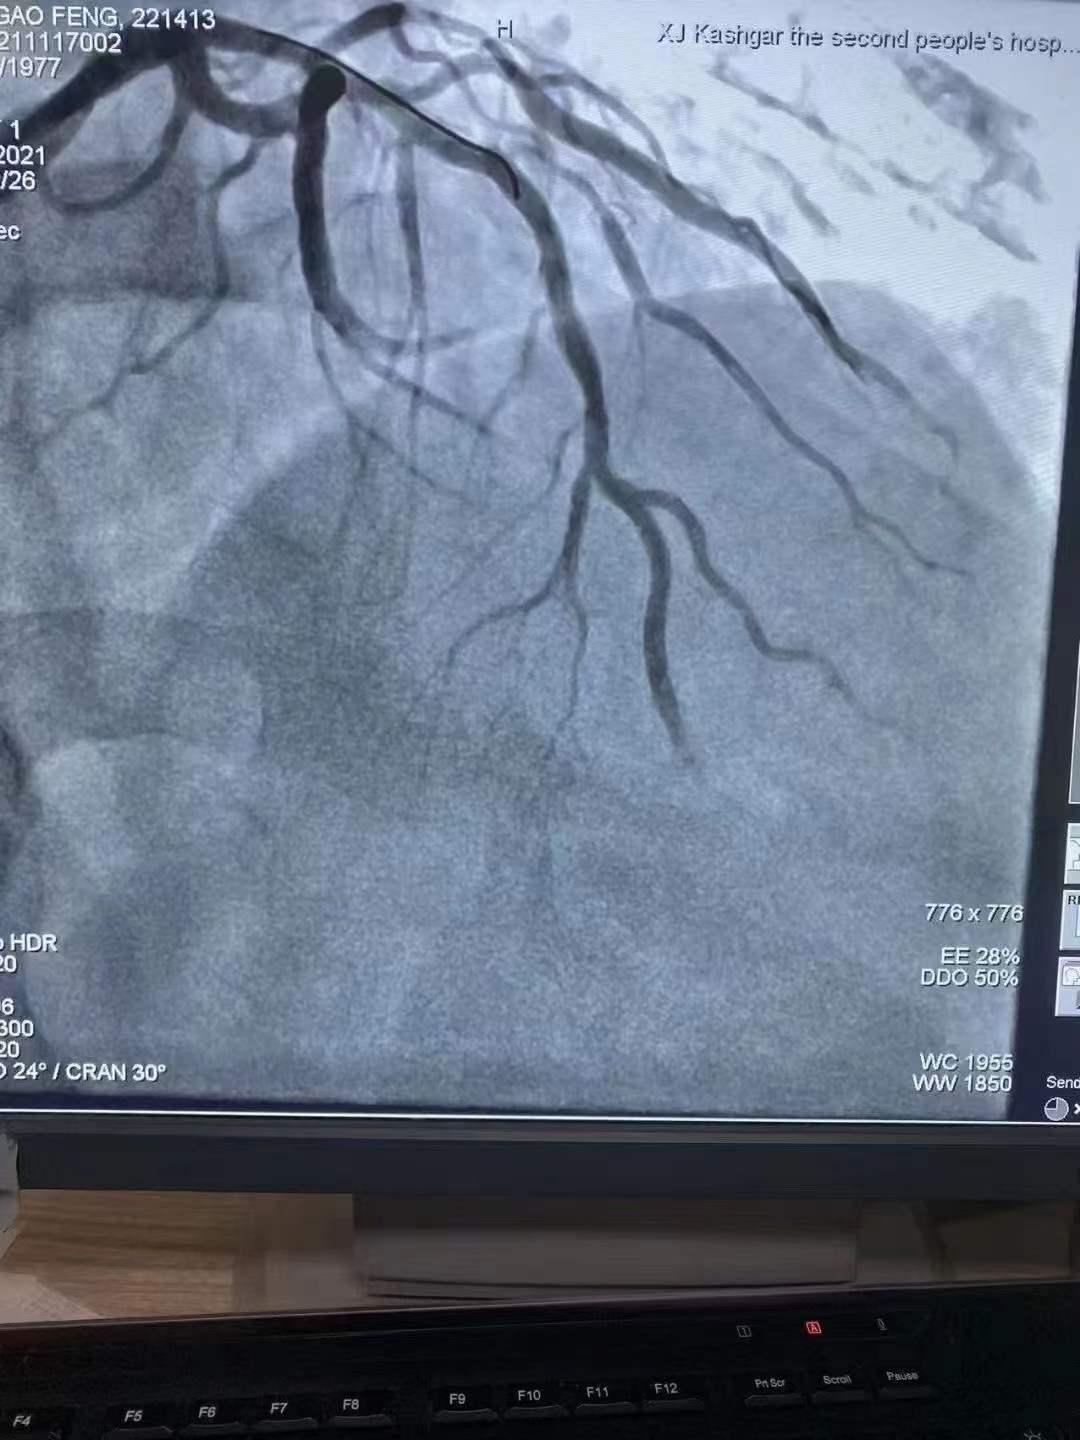

祝賀 新疆喀什地區(qū)第二人民醫(yī)院心內(nèi)科在復(fù)旦大學(xué)中山醫(yī)院援疆專家姚志峰主任帶領(lǐng)下成功為患者植入新疆首例Xinsorb生物可吸收支架,感謝援疆項(xiàng)目的扎實(shí)落地,溫暖了新疆各族百姓Xinsorb與白衣天使共同守護(hù)每一個(gè)心臟!

祝賀 新疆喀什地區(qū)第二人民醫(yī)院心內(nèi)科在復(fù)旦大學(xué)中山醫(yī)院援疆專家姚志峰主任帶領(lǐng)下成功為患者植入新疆首例Xinsorb生物可吸收支架,感謝援疆項(xiàng)目的扎實(shí)落地,溫暖了新疆各族百姓Xinsorb與白衣天使共同守護(hù)每一個(gè)心臟!